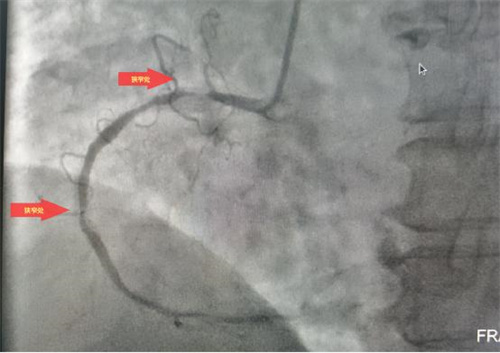

據(jù)了解,此次順利完成經(jīng)皮冠狀動脈內(nèi)支架植入術(shù)的患者共有4位,其中一名68歲老年女性患者,因胸悶氣促6余年,活動后明顯加重入院治療。經(jīng)冠脈造影檢查,發(fā)現(xiàn)左前降支次全閉塞、右冠99%重度狹窄,三支血管重度病變,情況危急。經(jīng)病情評估后,與患者家屬溝通,決定立即對右冠實施冠狀動脈球囊擴張加支架植入術(shù)。在上級專家的指導(dǎo)下,心病科團隊成功擴張了狹窄血管、植入支架,手術(shù)順利,患者術(shù)后安返病房,為患者后續(xù)治療創(chuàng)造了有力條件。

術(shù)后